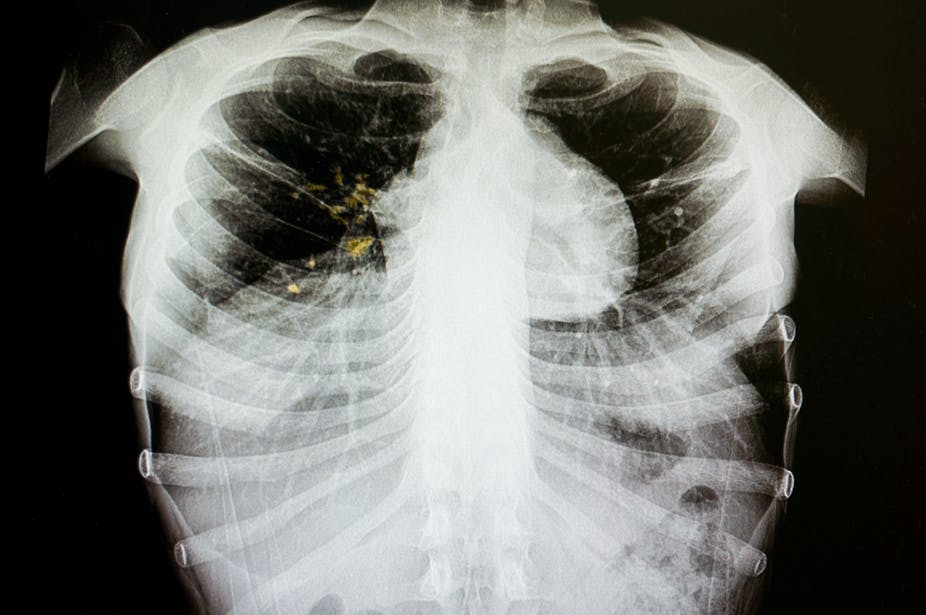

Around 18% of previously treated TB cases are drug resistant. Shutterstock